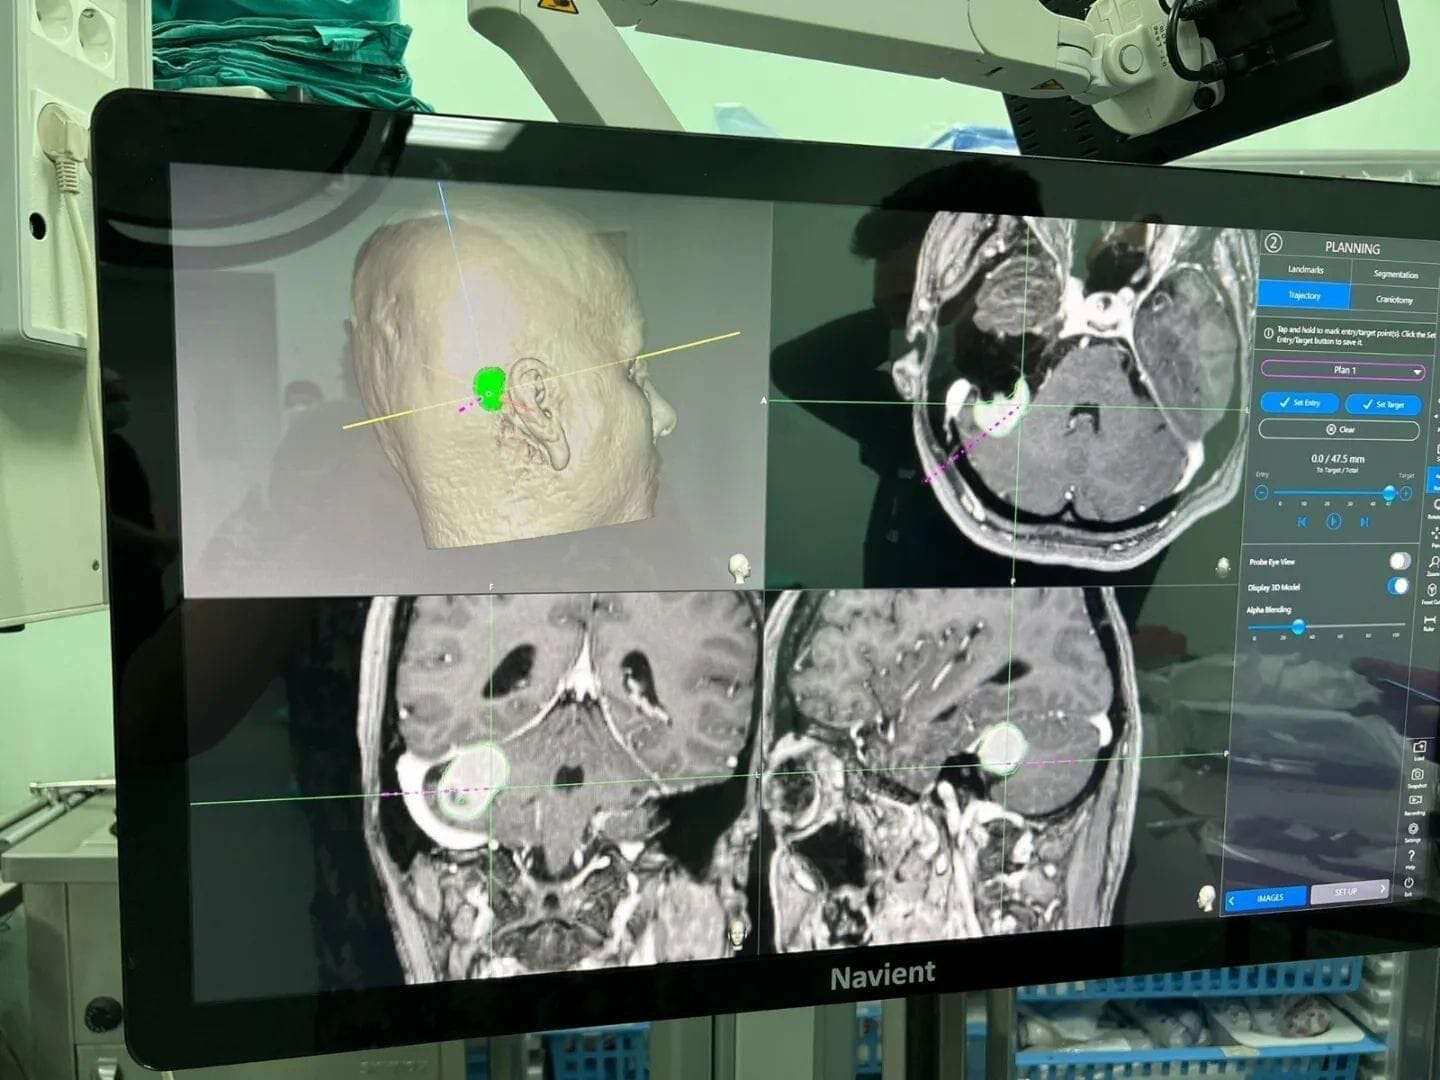

Daha önce teknik yetersizlikler nedeni ile Niğde’de yapılamayan ve hastaların başka şehirlere sevk edildiği köşe beyin tümörü ameliyatları, eksik cihazların giderilmesi ile artık Niğde’de yapılabiliyor.

Baş ağrısı ve baş dönmesi şikayetleri ile hastaneye başvuran 43 yaşındaki Figen Turgut’ta köşe tümörü olarak tabir edilen kulak arkasında beyin zarından kaynaklı bir kitle tespit edildi.

Yapılan tetkiklerin ardından ameliyat kararı alan Beyin Cerrahi Uzm. Op.Dr. Burak Yürük, Türkiye’de ileri merkezlerde kullanılan cihazların hastaneye alınması ile hastanın ameliyatını gerçekleştirdi.